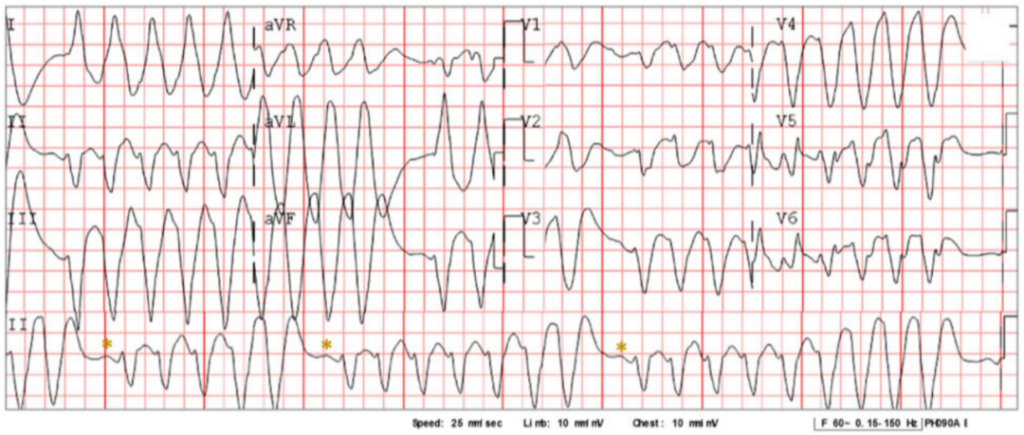

入院时心电图提示多形性室性心动过速,经诊断为氟卡尼中毒。

入院12导联心电图,提示宽QRS多形性心动过速,心率160次/分,QRS波群在5、7、9次循环逐渐变宽。